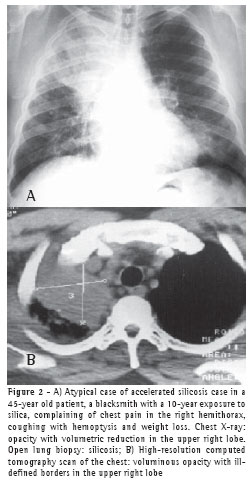

RESULTS

All 75 patients with accelerated silicosis were male. The mean age was 43 years (range, 28-76 years). The mean duration of exposure was 14.2 years (range, 7 months-38 years). Of the 75 patients, 62 (82.6%) were sandblasters, 11 (14.6%) were blacksmiths, 1 (1.4%) was a welder, and 1 (1.4%) was a metal polisher. In reference to concomitant tuberculosis, 39 patients reported a history of pulmonary tuberculosis (52%). Of those, 37 developed the disease during their exposure to silica.The diagnosis was confirmed in 31 cases: 24 through direct sputum smear microscopy; 3 through direct mycobacteria culture of the sputum; 1 through mycobacteria culture of the bronchoalveolar lavage fluid; and 3 through histopathology. In 8 patients, there was clinical and radiological suspicion of tuberculosis based on a response to specific treatment. The radiological classification of the large opacities seen on the chest X-rays was as follows: Type A in 23 patients (30.7%); Type B in 25 (33.3%); and Type C in 27 (36%) (Figures 1A and 1B). Of the cases analyzed, 74 presented bilateral conglomerate masses, whereas only 1 presented unilateral lesion (Figures 2A and 2B).

Of the 75 PMF patients, 44 underwent chest HRCT. The HRCT scans revealed that 88.6% of the masses were located in the upper thirds of the lungs and were posterior. Cavitations were observed in 18.18% of the masses, air bronchogram in 70.4% and internal calcification in 63.6%. Emphysematous lesions surrounding the masses were observed in 72.7%, and lymph node calcification was seen in 81.8% (Figures 3A and 3B).

Of the 75 cases analyzed, only 1 presented a large unilateral opacity

mimicking a tumor. The diagnosis of silicosis was made via thoracotomy with open lung biopsy. Isolated PMF lesions are frequently mistaken for lung cancer. Given the higher incidence of lung cancer in these patients, it is important to take a diagnostic approach in order to effectively differentiate malignant pneumoconiosis lesions from benign ones.(19)

In the present study, chest HRCTs revealed that the large opacities were predominantly (in 88.6% of the cases) located in the upper and posterior thirds of the lung.Air bronchograms and calcifications within the masses were found in over half of the patients. Calcified hilar and mediastinal lymph nodes were observed in 81% of the cases, 25% being of the eggshell type. Only 8 cases displayed cavitation within the masses, 6 presenting concomitant tuberculosis.